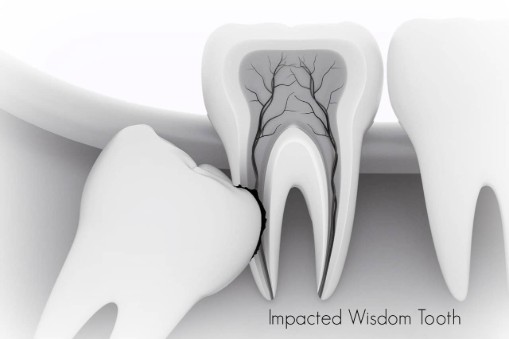

In most cases, inadequate space in the mouth does not allow the wisdom teeth to erupt properly and become fully functional. When this happens, the tooth can become impacted (stuck) in an undesirable or potentially harmful position. If left untreated, impacted wisdom teeth can contribute to infection, damage to other teeth, and possibly cysts or tumors.

There are several types, or degrees, of impaction based on the actual depth of the teeth within the jaw:

Complete Bony Impaction: The tooth is completely encased by jawbone. This will require more complex removal techniques.

Impacted Wisdom Teeth

What Is An Impacted Tooth?

Although most people develop and grow 32 permanent adult teeth, many times their jaws are too small to accommodate the four wisdom teeth. When inadequate space prevents the teeth from erupting they are called impacted. This indicates their inability to erupt into the proper position for chewing and cleaning.